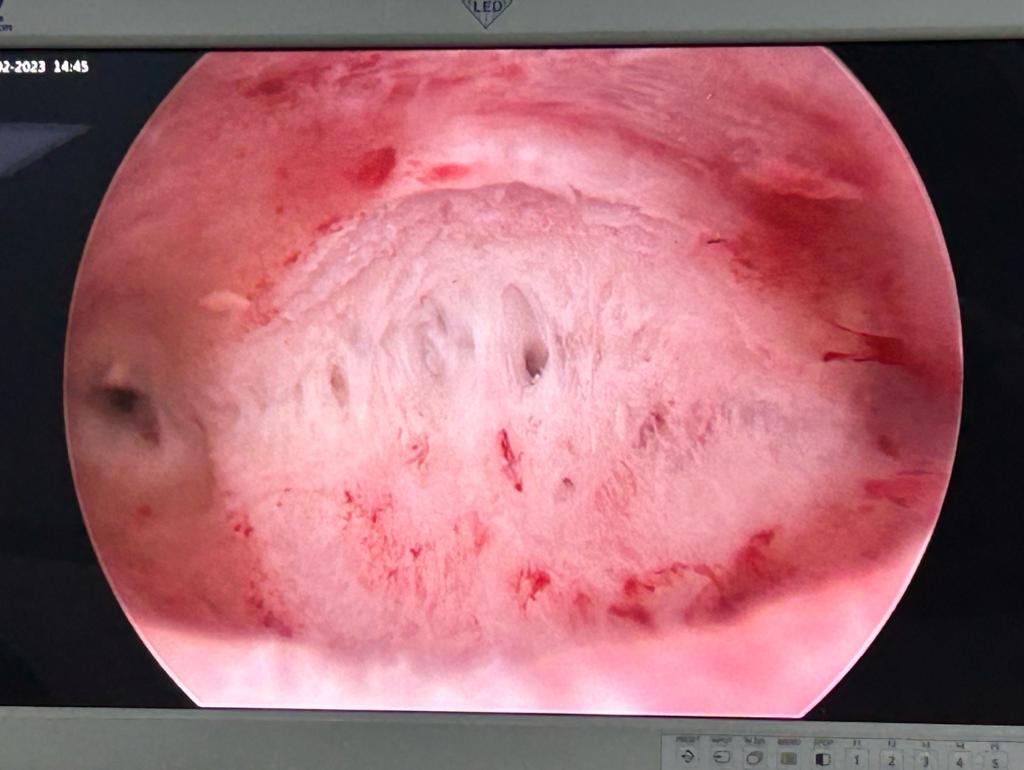

Infertile couple- treatment of Septum in Uterus - Hysterscopic treatment